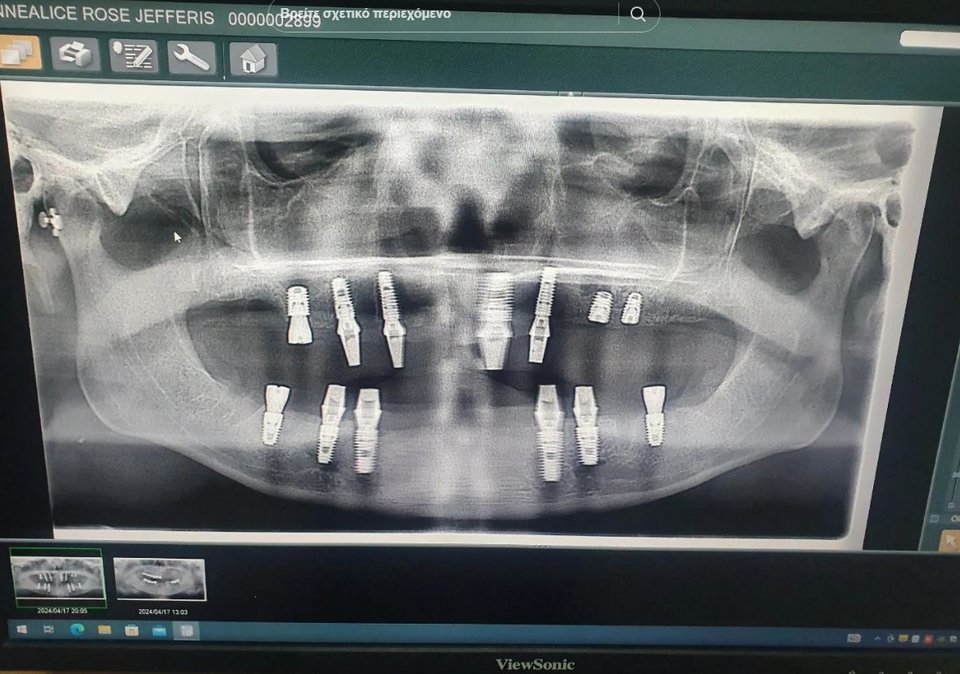

Δελεασμένη από τις διαφημίσεις στα μέσα κοινωνικής δικτύωσης και το χαμηλότερο κόστους της θεραπείας στο εξωτερικό, πήρε την απόφαση να πάει στην Τουρκία. Στις 8 Μαΐου 2024, επισκέφθηκε την ES Clinic για μια πρώτη συζήτηση. Ήξερε ότι θα χρειαζόταν να αφαιρέσει τα δόντια της και να τοποθετήσει βίδες για τα εμφυτεύματα, αλλά μετά από μια ακτινογραφία, ο οδοντίατρος την προειδοποίησε ότι η διαδικασία θα ήταν πολύ πιο περίπλοκη από ό,τι την είχαν κάνει να πιστέψει.

Ωστόσο, δεν ήταν όλα τόσο απλά όπως νόμιζε. Την ενημέρωσαν πως θα χρειαζόταν περισσότερες βίδες, ένα οστικό μόσχευμα και μια ανόρθωση των ιγμορείων προτού της τοποθετηθούν εμφυτεύματα. Η ανόρθωση των ιγμορείων είναι μια χειρουργική επέμβαση που περιλαμβάνει την τοποθέτηση ενός οστικού μοσχεύματος μεταξύ της άνω γνάθου και της μεμβράνης των ιγμορείων που βρίσκονται πιο κοντά στα πίσω δόντια. Η ιδέα είναι ότι η ανόρθωση των ιγμορείων θα συγχωνευτεί φυσικά με τη γνάθο, επιτρέποντας την τοποθέτηση ενός εμφυτεύματος.

Έναν μήνα όμως μετά την επέμβαση, άρχισε να αντιμετωπίζει προβλήματα με τα προσωρινά εμφυτεύματα, τα οποία οδήγησαν στο σχηματισμό φουσκάλων στη μύτη της, και το πρόσωπό της παραμορφώθηκε. Τα προσωρινά δόντια που της είχαν τοποθετηθεί μόλις ένα μήνα πριν άρχισαν να πέφτουν, αποκαλύπτοντας τις βίδες που έμοιαζαν με μανταλάκια. Στη συνέχεια, η πλάκα που συγκρατούσε το εμφύτευμα στη θέση του έσπασε.